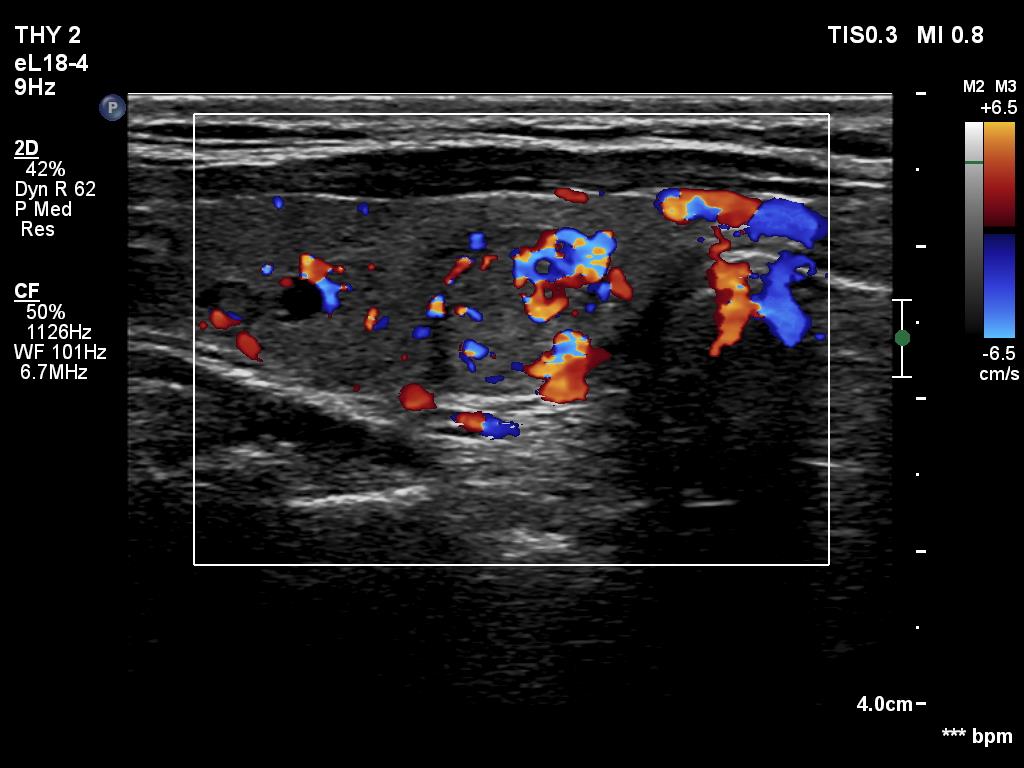

Ultrasonography. The thyroid was echonormal or minimally hypoechogenic. There was an iso/hyperechoic nodule in the right lobe. The lesion had halo and sowed taller-than-wide shape. The vascularity was not specific.